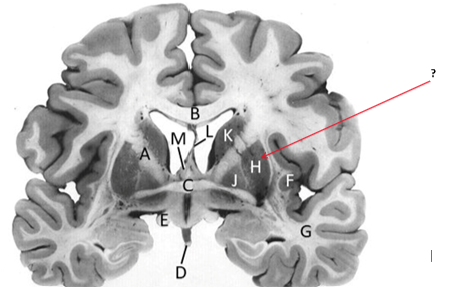

Name this and state its function.

Corpus Callosum.

Putamen.

Name this, state its function, pathways and cellular components.[5 marks]

Caudate nucleus.

Medium spiny neurons utilising GABA and some Cholinergic.

From cortex–>CN–>hippocampus, Gp and thalamus.

Septum pellucidum.

Fornix.

Anterior commissure.

Interconnects:

Infundibular stalk.

Insula.

Name this, state its function, components[2] and the difference in pathways.

Internal capsule.

Anterior limb:

Posterior limb:

Corticospinal tracts and corticopontine tracts: